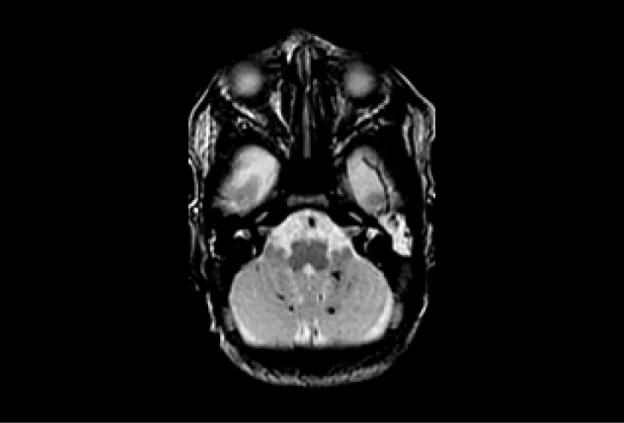

Macroscopic brain development – cortical folding. Three-dimensional reconstructions of cortical white matter volumes from MRI scans taken at 24 weeks to term gestation showing the development of cortical folding and surface curvature. The white matter surface from a term newborn with hypoplastic left heart syndrome displays noticeably less cortical folding and smoother surface curvature than a term newborn without heart disease.